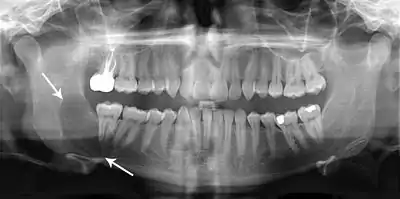

Radiographs of odontogenic keratocysts show well-defined radiolucent areas with rounded or scalloped margins which are well demarcated.[12] These areas can be multilocular or unilocular. The growth pattern of the lesion is very characteristic from which a diagnosis can be made as there is growth and spread both forward and backward along the medullary cavity with little expansion. No resorption of teeth or inferior dental canal and minimal displacement of teeth is seen. Due to lack of expansion of the odontogenic keratocyst, the lesion can be very large when radiographically discovered.[9]